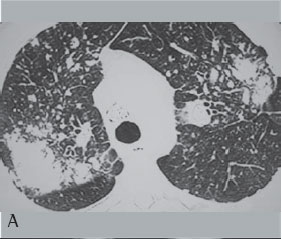

Dos 75 pacientes portadores de FMP, 44 realizaram TCAR de tórax. Quanto às características das massas analisadas pela TCAR de tórax verificou-se que 88,6% predominaram nos terços superiores e eram posteriores. Escavações foram observadas em 18,18% das massas, broncograma aéreo em 70,4% e calcificação no interior das mesmas em 63,6% delas. Enfisema ao redor das massas foi observado em 72,7% e calcificação linfonodal em 81,8% dos casos (Figuras 3A e 3B).

Neste estudo, na TCAR de tórax as grandes opacidades predominaram nos terços superiores e posteriores dos pulmões (88,6%). Broncogramas aéreos e calcificações no interior das massas ocorreram em mais da metade dos pacientes. Linfonodos hilares e mediastinais calcificados foram observados em 81% dos casos, sendo 25% do tipo casca de ovo. Apenas 8 casos apresentaram escavação no interior das massas, sendo que 6 deles apresentavam tuberculose associada.